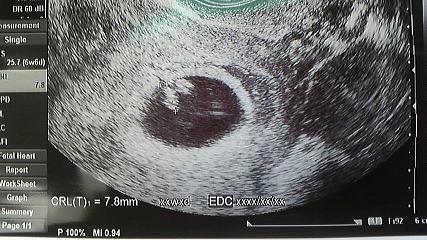

心拍が確認できた時のエコー写真、6w4d。